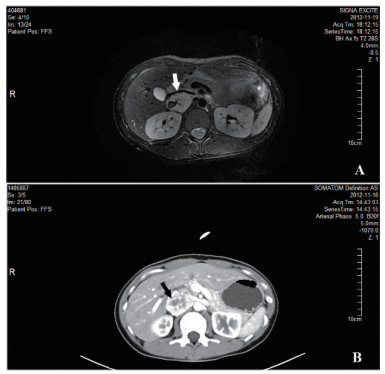

患者2,女,73岁,因“发现血糖升高13年,反复心悸出汗1年”入住我科。入院后监测血糖波动于3.2~22.6 mmol/L,血压波动于77~223/38~90 mmHg。尿VMA 88.20μmol/24h(0.1-68.6)。腹部CT:左侧肾上腺见一不规则肿块,大小35.3 mm×19.9 mm×29.4 mm,考虑嗜铬细胞瘤(图 3)。术前予特拉唑嗪口服4周,血压控制基本平稳。术前24 h血压波动在99~134/55~66 mmHg。手术当日停用特拉唑嗪,全麻下行腹腔镜左肾上腺肿瘤切除术。术中治疗监测血压波动于110~166/42~69,手术过程顺利,持续约50 min,术中出血约10mL。术后转入重症监护室。术后7 h出现血压下降,予扩容及血管活性药物维持血压仍偏低,术后10 h复查血常规血红蛋白45 g/L,较前明显下降,超声提示腹腔内大量积血。考虑腹腔大量出血,行腹膜后探查+血肿清除止血术,术后血红蛋白稳定,血压稳定。手术病理:(左肾上腺)嗜铬细胞瘤。出院时血压126/70 mmHg左右,未使用降压药物。予甘精胰岛素、阿卡波糖及西格列汀控制血糖,血糖控制在8~10 mmol/L左右。

图 2 腹部CT:左侧肾上腺见一不规则肿块,大小35.3 mm×19.9 mm×29.4 mm(前后×左右×上下),边界清,平扫密度不均,增强扫描明显不均匀强化,中心见不规则囊变坏死区,提示左侧肾上腺占位,考虑嗜铬细胞瘤(箭头)